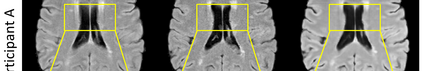

Multiple Sclerosis (MS) is a chronic progressive neurological disease characterized by the development of lesions in the white matter of the brain. T2-fluid-attenuated inversion recovery (FLAIR) brain magnetic resonance imaging (MRI) provides superior visualization and characterization of MS lesions, relative to other MRI modalities. Longitudinal brain FLAIR MRI in MS, involving repetitively imaging a patient over time, provides helpful information for clinicians towards monitoring disease progression. Predicting future whole brain MRI examinations with variable time lag has only been attempted in limited applications, such as healthy aging and structural degeneration in Alzheimer's Disease. In this article, we present novel modifications to deep learning architectures for MS FLAIR image synthesis, in order to support prediction of longitudinal images in a flexible continuous way. This is achieved with learned transposed convolutions, which support modelling time as a spatially distributed array with variable temporal properties at different spatial locations. Thus, this approach can theoretically model spatially-specific time-dependent brain development, supporting the modelling of more rapid growth at appropriate physical locations, such as the site of an MS brain lesion. This approach also supports the clinician user to define how far into the future a predicted examination should target. Accurate prediction of future rounds of imaging can inform clinicians of potentially poor patient outcomes, which may be able to contribute to earlier treatment and better prognoses. Four distinct deep learning architectures have been developed. The ISBI2015 longitudinal MS dataset was used to validate and compare our proposed approaches. Results demonstrate that a modified ACGAN achieves the best performance and reduces variability in model accuracy.